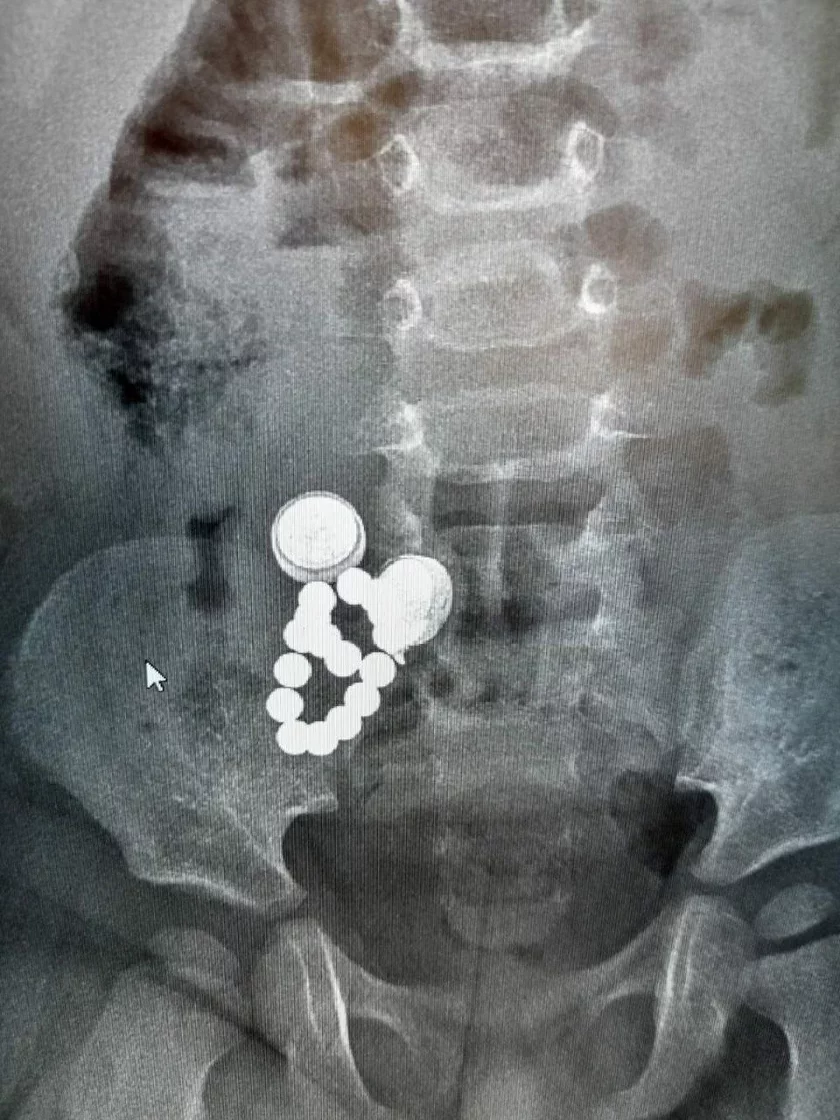

Дзіця ўзростам усяго 1,8 года было шпіталізаванае ў Дубровенскую бальніцу са страўнікава-кішачным крывацёкам. Пры абследаванні аказалася, што ў яго страўніку і кішэчніку аказаліся 2 батарэйкі, 16 магнітаў і шруб.